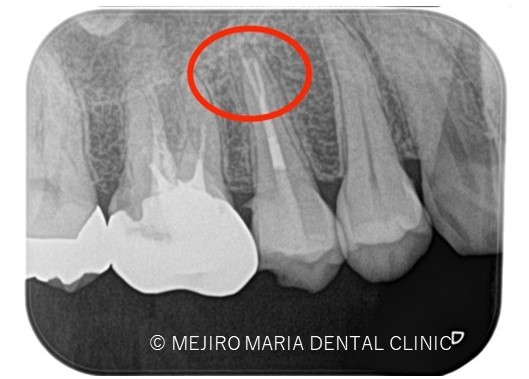

*赤丸で示しているところは、根が分岐している箇所を示す

診査の結果、右上5番の歯髄には歯髄生活反応は確認できず、歯髄壊死が起因となる根尖性歯周炎と診断しました。術前のレントゲン診査により、根尖が2つに分岐していることを確認できます。

今回は右上5番に対しての根管治療における、根尖3mmで分岐する根管へのアプローチでした。

一度見失った根管は通常の根管治療では追従が難しくなるため、感染を根管内に留めてしまう原因となります。その為、術前のレントゲン診査が非常に重要となります。